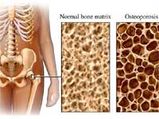

Youth Prone To Osteoporosis

Youth Prone To Osteoporosis -